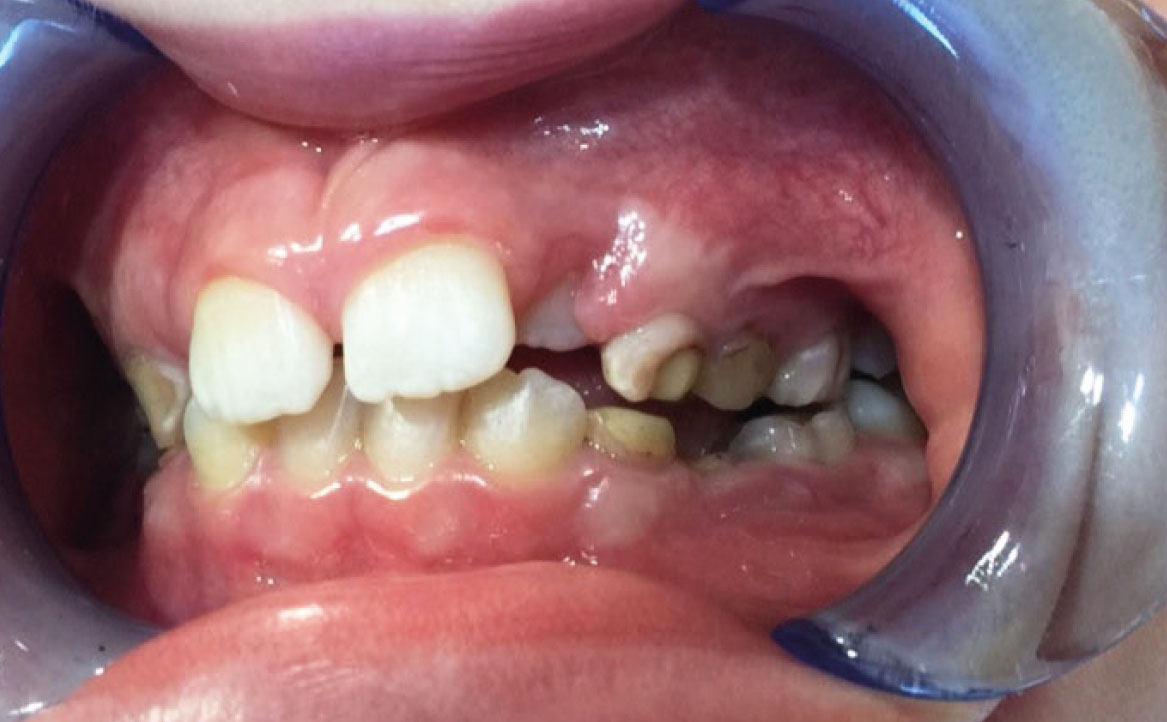

A seguito del trattamento è stato osservato un miglioramento dell’igiene orale (fig. 5).

Dall’esame obiettivo intra orale si osservava una seconda classe canina destra e sinistra, una seconda classe molare destra e sinistra, e un diametro inter-canino e inter-molare ridotto sia in riferimento al mascellare superiore sia al mascellare inferiore (fig. 3A-3E).

Clinical examination revealed high caries risk, poor oral hygiene, and constricted upper and lower arches.